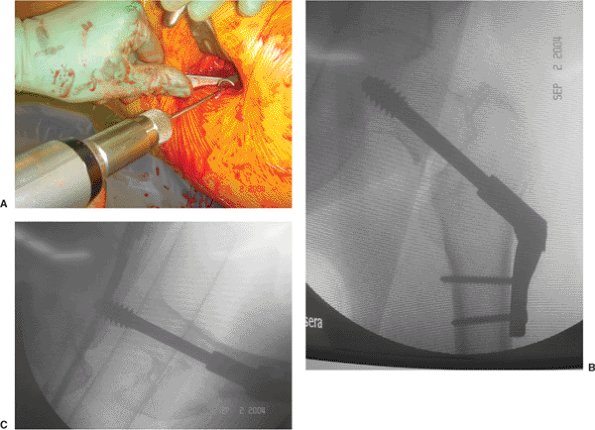

Figure 16.14. A. Tapping of the proximal femur under image intensification to the (B) final, seated, lag-screw position to prevent femoral head rotation during lag screw insertion.

the proximal femur. With the VHS system, if the side plate does not

parallel the lateral cortex, one can adjust the plate angle using a

screw driver to move the mechanism that controls the side plate–barrel

angle (Fig. 16.17). Once the plate has been

inserted and placed against the bone, it is loosely clamped to the

femoral shaft and the fracture is impacted by releasing the traction on

the extremity and gently displacing the femoral shaft toward the

proximal fragment. This impaction maneuver is thought to enhance

fracture stability. The plate-holding screws are then inserted (Fig. 16.18).

Figure 16.17. The side plate is impacted against the lateral cortex of the proximal femur. With the VHS system, (A) if the side plate does not parallel the lateral cortex, (B) one can adjust the plate angle using a screw driver to move the (C) worm gear that controls the side plate–barrel angle.